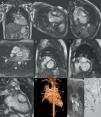

A 27-year-old male with known congenitally corrected transposition of the great arteries was referred for further workup due to increasing arrhythmias. Cardiovascular magnetic resonance (CMR) showed situs solitus and atrioventricular (AV) and ventriculoarterial (VA) discordance, with the aorta lying anteriorly and to the right of the pulmonary trunk (Figure 1). An unusual alignment was found, with the right and left ventricular inflow tracts aligned almost perpendicular to one another, precluding imaging all four chambers in one plane. The systemic right ventricle was relatively hypoplastic and lay superior to the subpulmonary left ventricle. The findings were typical of a previously unnoticed criss-cross atrioventricular arrangement. A large nonrestrictive ventricular septal defect and severe pulmonary stenosis were also present; biventricular ejection fraction and indexed volumes were normal and there was no myocardial fibrosis. Antiarrhythmic treatment and an electrophysiological study were proposed.

Balanced steady-state free precession (b-SSFP) cine images depicting normal situs (A) and atrioventricular (AV) and ventriculoarterial discordance (B and C, respectively). Note the aorta arising anteriorly and to the right of the pulmonary artery (D). An important clue to the diagnosis of criss-cross heart is the inability to image flow across the two AV valves in the same plane. b-SSFP cine images show this unusual arrangement of the AV valves, perpendicular to one another (E), with the subpulmonary left ventricle (LV) located inferiorly and the smaller systemic right ventricle (RV) superiorly, resulting in a twisted appearance (G); a large (approximately 20 mm) non-restrictive ventricular septal defect is also noted, with bidirectional flow (F). Contrast-enhanced 3D magnetic resonance angiography was performed to help delineate the anatomical relations described above and to assess the great vessels and their branches (H). Phase-contrast velocity mapping of pulmonary stenosis, located at both sub-valvular (from an indented ridge) and valvular level, a common feature of this congenital cardiac anomaly (I). Ao: aorta; LV: left ventricle; PA: pulmonary artery; PAVV: pulmonary AV valve; PV: pulmonary valve; RA: right atrium; RV: right ventricle; SAVV: systemic AV valve; VSD: ventricular septal defect.